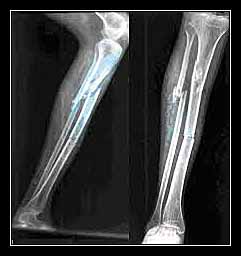

- Về sau, bệnh Lobstein, hoặc “xương thủy tinh” (bệnh xương giòn, bệnh tạo xương bất toàn) kèm với năng tĩnh nhão ở dây chằng, xương mảnh khảnh, củng mạc màu xanh, sọ rộng “có bờ”, đôi khi điếc.

- Bệnh xương hóa đá hoặc bệnh xương đá cẩm thạch Albers – Schonberg.

Ở TRẺ EM VÀ THANH NIÊN: gãy xương tự phát có thể phát hiện: . Sarcom xương,

NHUYỄN XƯƠNG: Xương không gãy hoàn toàn mà “giả gãy xương” đó là vân Looser – Milkmann: Vân mất calci thẳng đứng hoặc nghiêng đối với mặt xương hình thẳng hoặc ngoằn ngoèo, thường là đối xứng các vân này nằm trên cổ xương cánh tay và cổ xương đùi, ở các nhánh xương mu, xương sườn, bờ nách của xương bả vai.

- Trong bệnh còi xương của trẻ em, có thể gặp gãy xương cành tươi.

LOÃNG XƯƠNG: Xương sườn, cổ xương đùi, nhất là gãy do lụn nén thân đốt sống (nhất là loãng xương trong tăng năng vỏ thượng thận).

TẢNG NÀNG TUYẾN CẬN GIÁP (tăng calci – huyết, giảm phospho – huyết; gãy các xương dài và đốt sống, nhiều nơi khám phá được nhờ chụp X-quang; (trong bệnh Paget, gãy xương hiếm thấy và không hoàn toàn, ở xương đùi, xương chày).

DI CĂN XƯƠNG: ung thư vú, thận, phổi, tuyến tiền liệt, tuyến giáp. Xương bị gãy, trên phim X-quang có hình biến chất rõ rệt.